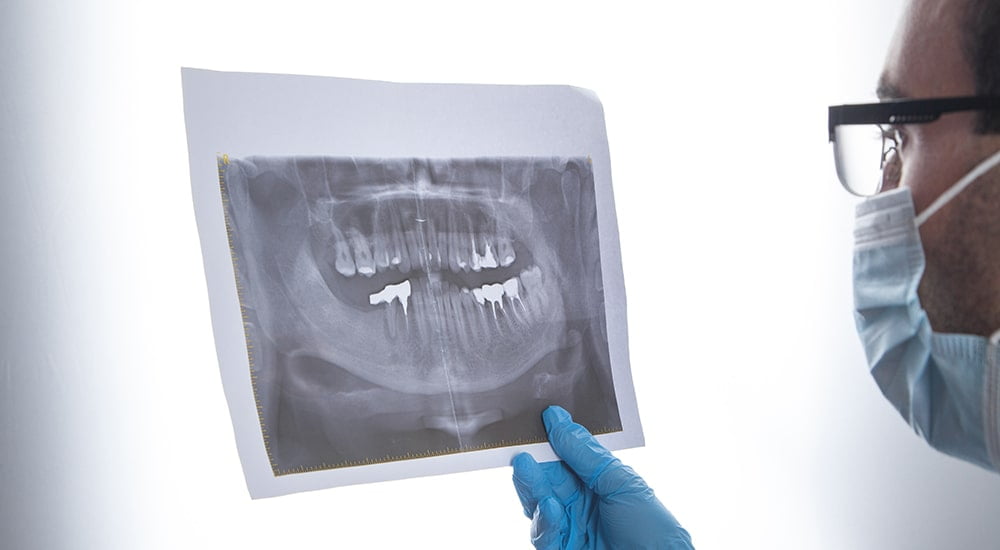

Hastanın ağzının içerisinde kırık diş olup olmadığı fiziki muayene ve çekilecek röntgen ile belirlenebilir. Kırılan bir dişin hangi yöntemle tedavi edileceği, dişte oluşan hasara göre hasta özelinde belirlenir. Uygulanabilecek tedavi seçenekleri arasında; yapıştırma, kron, kozmetik şekillendirme, kaplama ve kanal tedavisi bulunur. Diş kırılmalarının tedavisi çoğu zaman geride kalan sağlıklı diş dokusu miktarı değerlendirildikten sonra dolgu ya da kron ile yapılabilir. Diş çürüğüne bağlı olarak meydana gelen kırıklarda diş restorasyonu yapılmadan önce dişteki çürük dokusu temizlenmelidir.